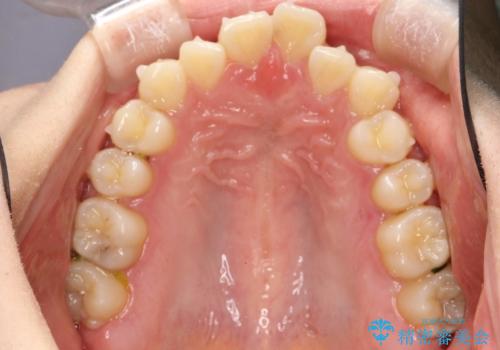

インビザラインによるガタつきの矯正治療 シンプル・短期間

- 非抜歯、IPR+拡大によるマウスピース矯正を計画した。

一見前歯のガタつきだけのように見えても、そのガタつきの根本的な原因が奥歯の位置であったりすると、マウスピースの枚数がそれなりに多くなり、治療に時間がかかることもあります。